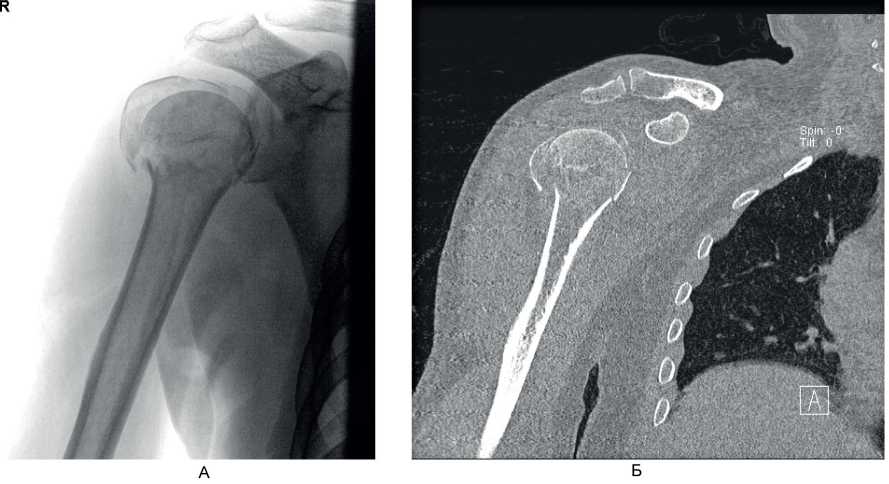

На контрольном осмотре через 6 мес у 7 (63,6 %) пациентов этой группы отмечено полное восстановление функции в плечевом суставе, у 4 (36,4 %) больных – небольшое ограничение движений и боль при движениях. Клинический пример 1. Больная М., 60 лет, поступила во ВЦЭРМ им. А.М. Никифорова в экстренном порядке. При поступлении выполнены рентгенография плечевого сустава в стандартных проекциях (рис. 6А) и компьютерная томография (см. рис. 6В). Перелом по классификации АО – В3. На 2-е сутки после поступления выполнено оперативное вмешательство – БИОС перелома хирургической шейки правой плечевой кости (см. рис. 6В).

Рис. 6. Больная М., 60 лет. А – рентгенография; Б – компьютерная томография поврежденного сегмента конечности; В – контрольная рентгенография в 1-е сутки после операции (косая проекция)

Клинический пример 2. Больной А., 50 лет, поступил в клинику ВЦЭРМ им. А.М. Никифорова в экстренном порядке. Выполнены рентгенография плечевого сустава в стандартных проекциях (рис. 8А), и компьютерная томография (см. рис. 8Б).

Рис. 8. Больной А., 50 лет. А – рентгенография плечевого сустава в стандартных проекциях; Б – компьютерная томография до операции

Перелом по классификации АО – С3.1. На 2-е сутки после поступления выполнено оперативное вмешательство – БИОС хирургической шейки правой плечевой кости. Рентгенография на 1-е сутки после операции представлена на рис. 9А, Б, контрольная рентгенография плечевого сустава через 6 мес после операции – на рис. 9В. Функциональный результат после операции – на рис. 10.

Рис. 9. Больной А., 50 лет. А, Б – рентгенография на 1-е сутки после операции; В – через 6 мес после операции